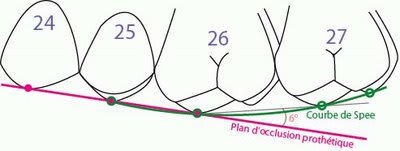

> quand on voit une aussi belle courbe de spee, on peut être sur que l'occlusion

> est bien réglée !

ahah! c´est vrai, il n y a pas du tout de courbe de spee!!!! :-)

Dans ce cas ici,La prothèse qu avait le patient avant l opération n avait pas de courbe non plus et le patient n avait pas de problème avec sa musculature ....alors comme c etait plus simple de reprendre l occlusion de la prothèse avant.....surtout qu on a remplacé seulement à la position 6.

Personnellement, j'aurais bien changé l'occlusion: je trouve qu'il est dommage d'adapter un aussi beau travail à un appareil complet maxillaire dont le concept occlusal est particulier.

Imagine toi en train de faire un bridge complet sur implant en haut aussi par la suite: tu serais obligé de reproduire à nouveau ces erreurs de conception occlusales.